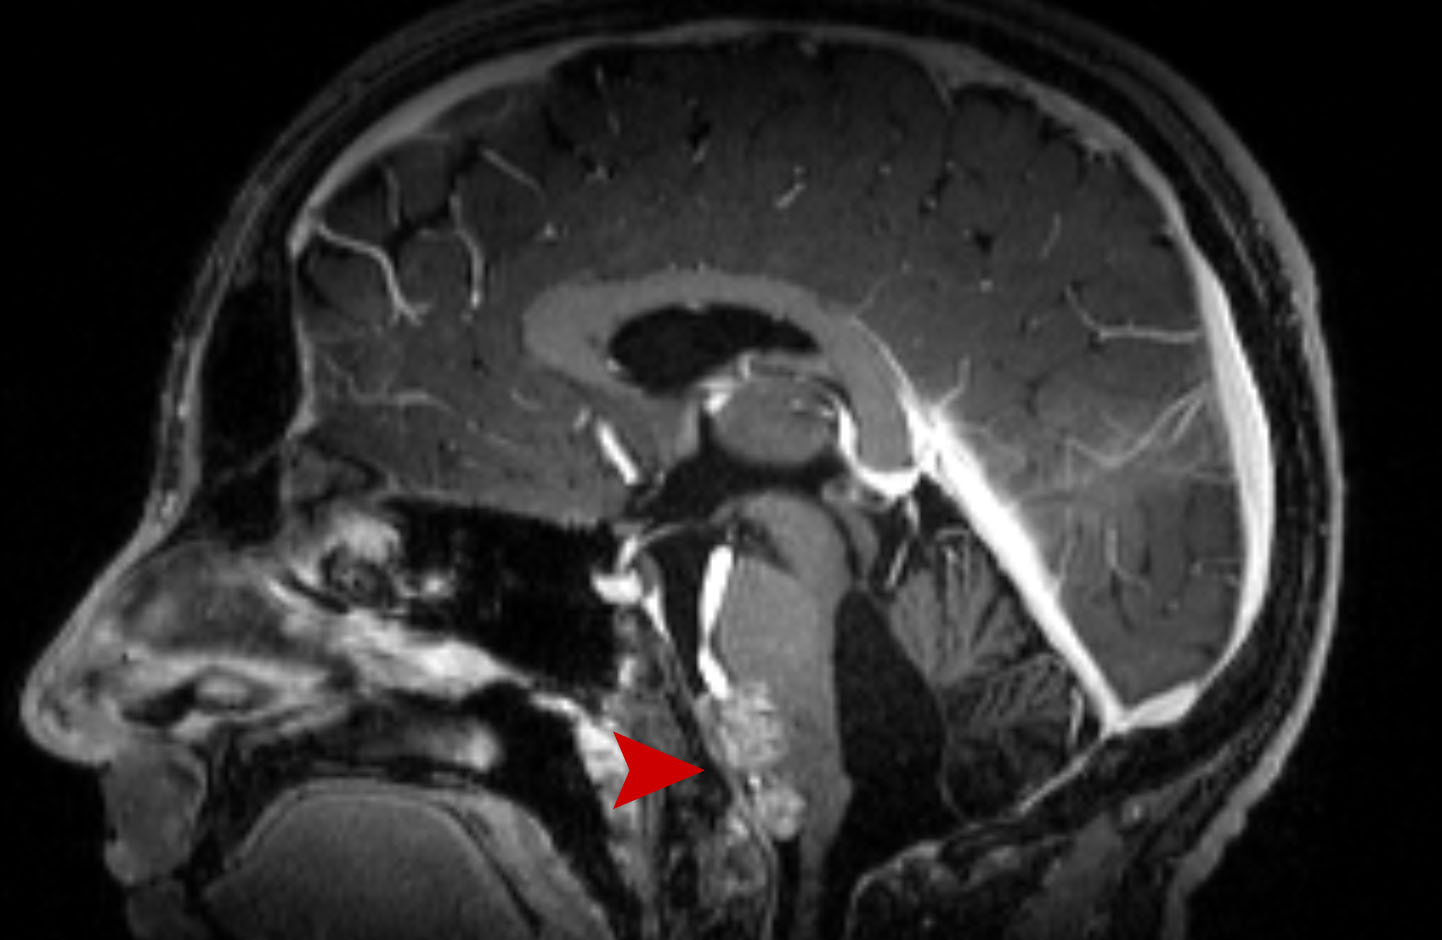

Μηνιγγίωμα Θεραπεία με CyberKnife #30

Θήλυ 70 ετών με μηνιγγίωμα Ινιακού τρήματος αριστερά με συνοδά πιεστικά φαινόμενα στον προμήκη. Σύγκριση…